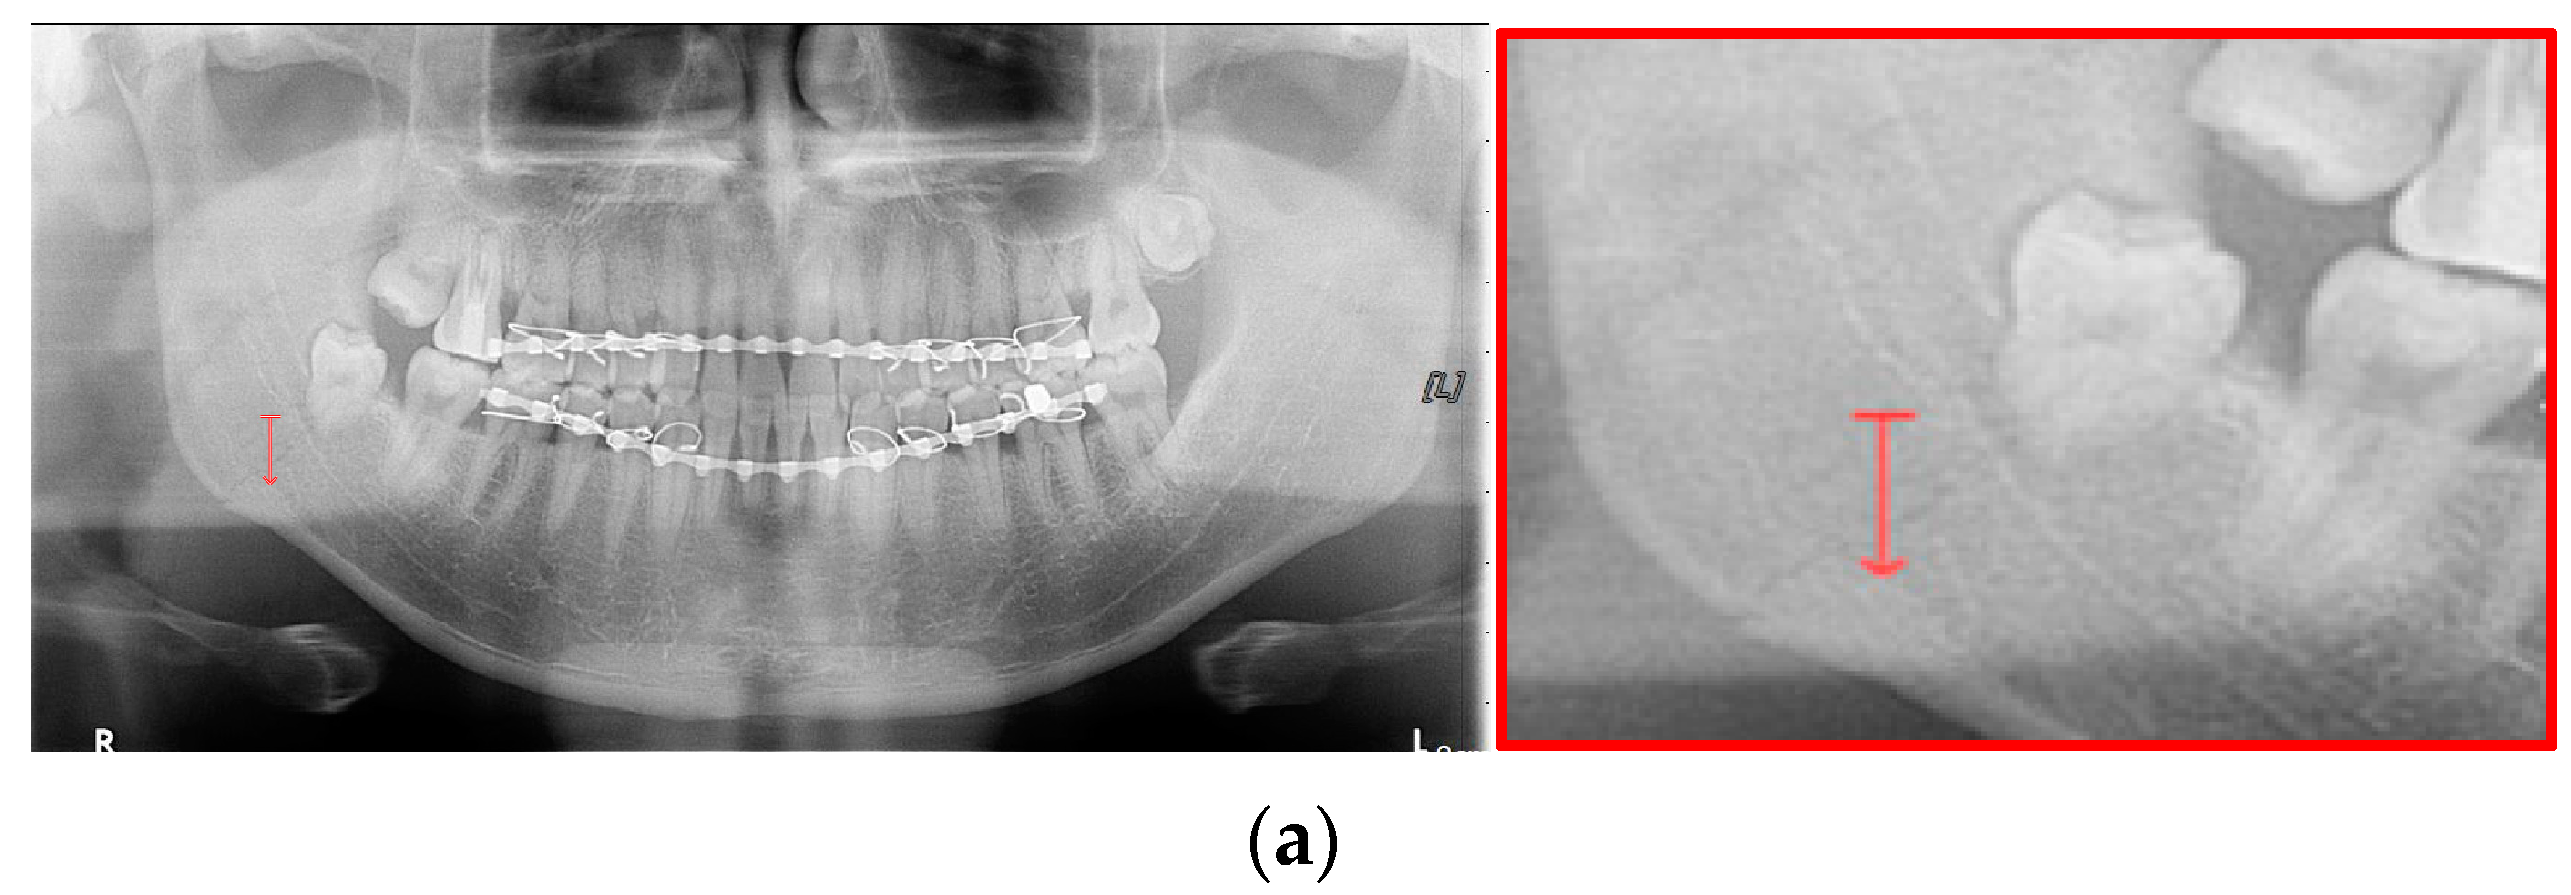

In Table 6, the parameters used for training are indicated, and in Figure 11, Figure 12 and Figure 13, the results of the doctor’s diagnosis, Mask R-CNN, YOLOv4, U-Net, LAT YOLOv4, and U-Net withYOLOv4 are compared. Figure 11 illustrates fractures in the angle and condylar regions, and in Mask R-CNN, the symphysis is misdiagnosed as a fracture. In Figure 12, the Mask R-CNN misdiagnoses the symphysis as a fracture, the result of the fact that the YOLOv4 module has better performance detecting angle fractures rather than does the LAT YOLOv4, as shown in Figure 12c,e. In short, the LAT-processed image does not always have the advantage of better revealing fractures compared with the normal panoramic radiograph.

Figure 11.

The comparison of mandibular fracture detection: (a) oral and maxillofacial radiologist, (b) Mask R-CNN (with colored polygons and boxes), (c) YOLOv4, (d) U-Net (with a red line), (e) LAT YOLOv4 (with red boxes), and (f) U-Net with LAT YOLOv4 (with a red box and lines).